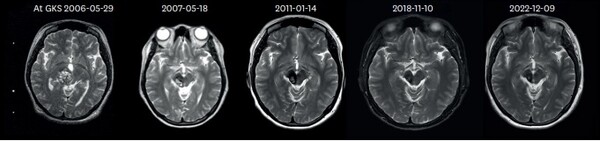

서울대병원 신경외과 백선하 교수 연구팀은 1998년부터 2012년까지 감마나이프 방사선 수술을 받은 CCM 환자 233명 중, 10년 이상 추적 관찰이 가능한 79명을 대상으로 ‘장기 예후’를 분석했다. 감마나이프 방사선 수술 전후의 ▲연간 출혈률(AHR) ▲신경학적 회복 정도 ▲방사선 관련 부작용(ARE) ▲병변 크기 변화를 분석했으며, 평균 추적 기간은 14년이었다.

79명 환자들의 예후를 분석한 결과, 수술 전에는 출혈률이 21.4%였다가 수술 후 2년차에 3.8%, 10년차에 1.4%로 감소했음을 확인했다. 이후에는 약간 증가해 2.3% 수준으로 유지됐다. 특히 CCM이 뇌간에 위치했던 환자의 경우, 수술 전 출혈률이 27.2%였으나 수술 후 2년차에 6%, 10년차에 3.5%로 감소했다.

신경학적 결손을 보였던 환자 중 74.3%는 마지막 관찰 시 증상이 회복되었으며, 병변의 81.3%는 크기가 줄어든 것을 확인했다. 6.4%의 환자가 방사선 부작용을 겪었으나 이로 인한 사망자는 없었다.